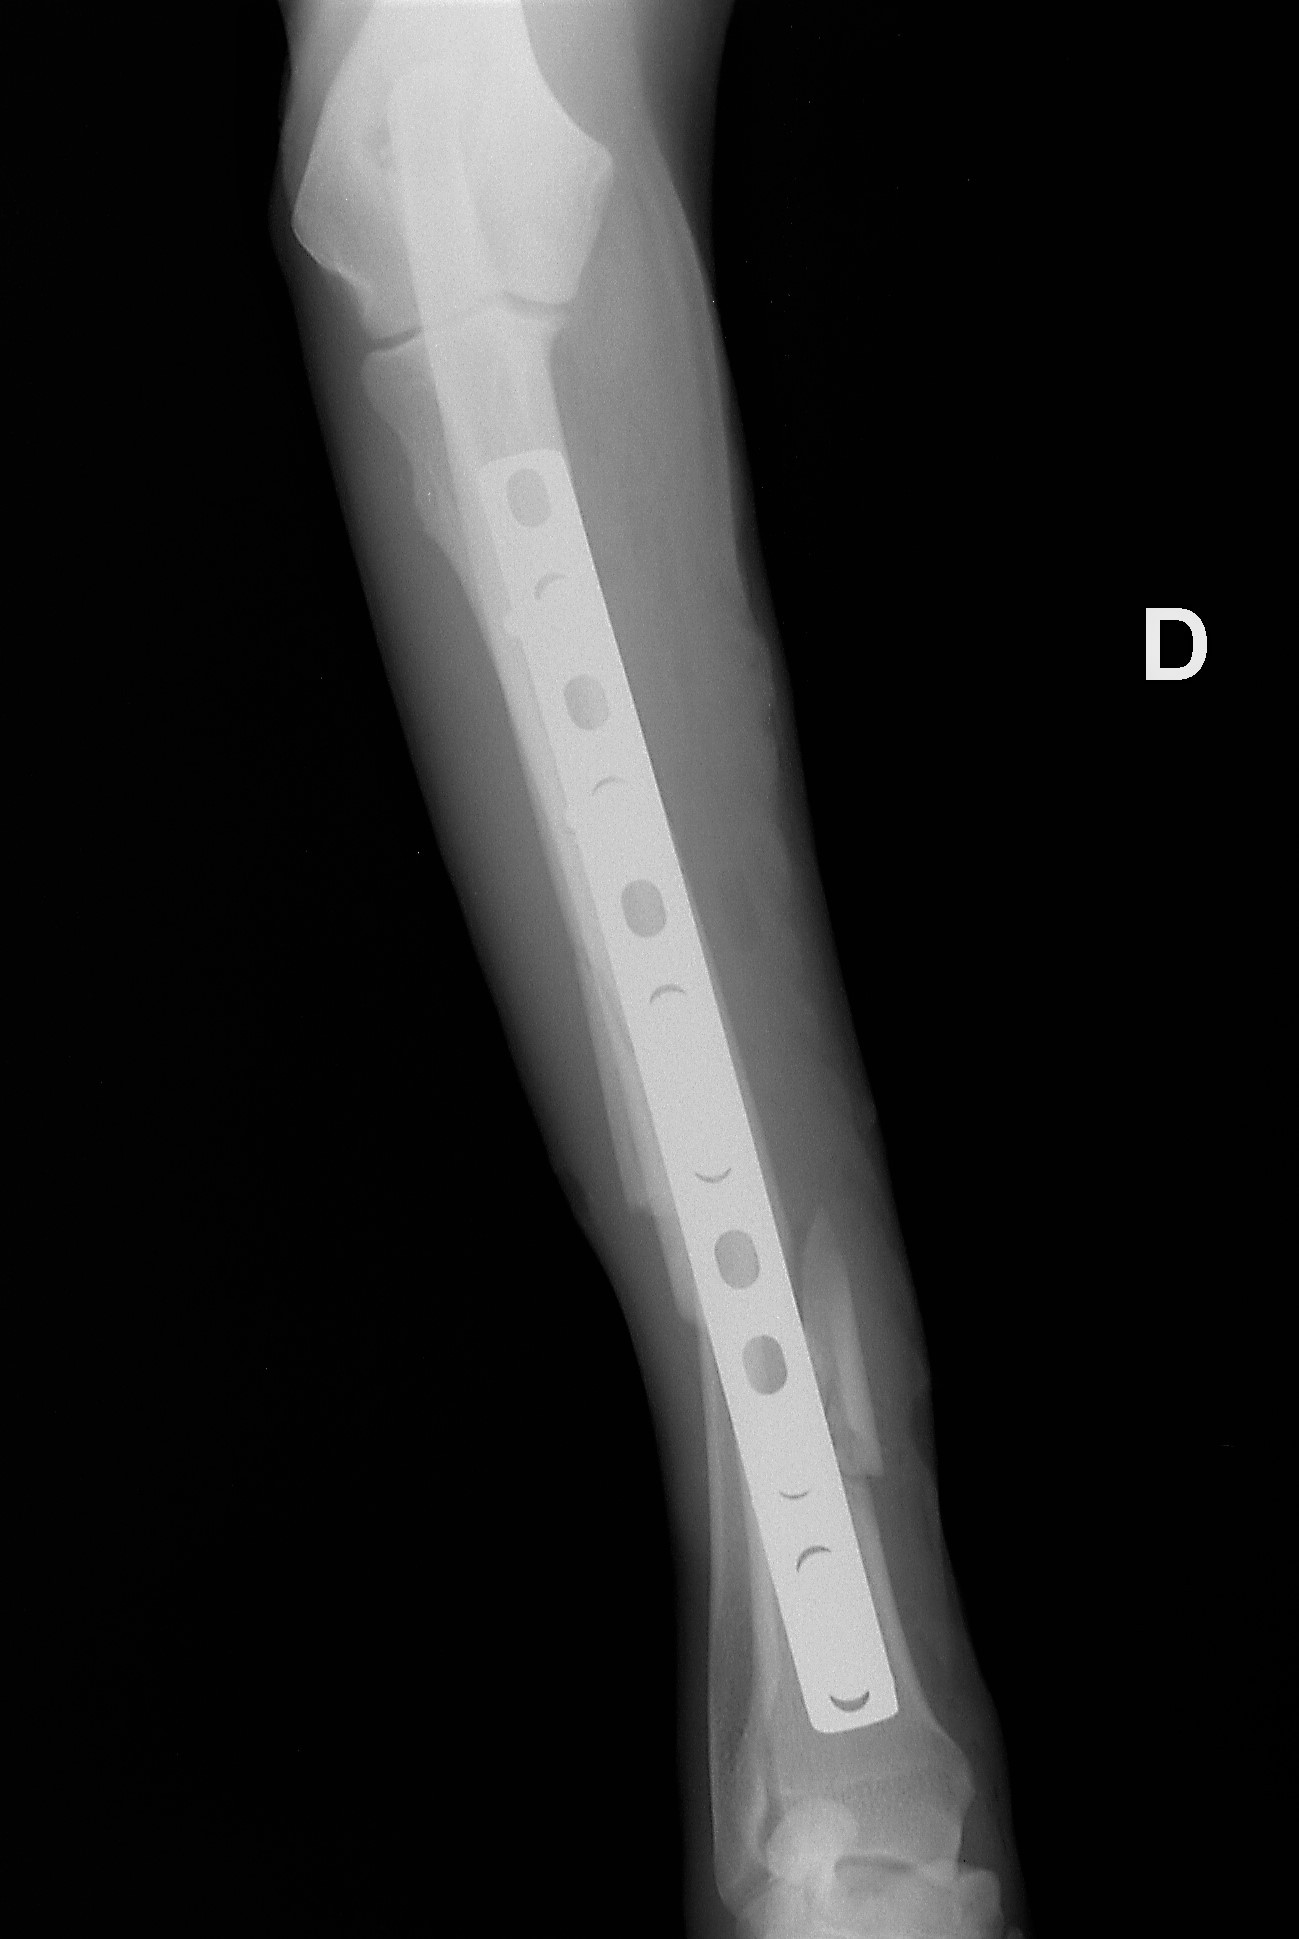

Noppe L, Noppe J, Réveillé D, Simar L, Watrin E

Chiens, chats NAC

Médecine généraliste et urgentiste, chirurgie générale tissus mous / tissus durs, hospitalisation